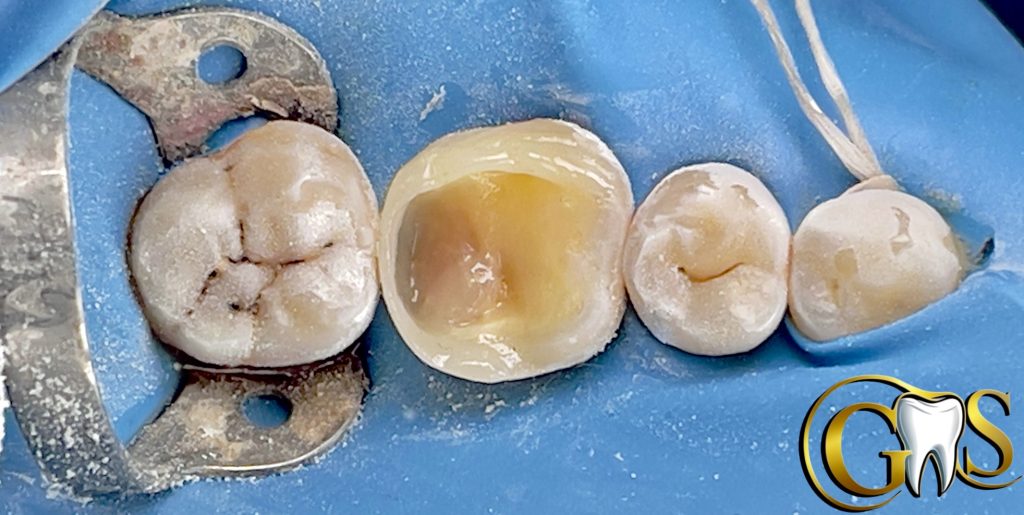

Saving vitality of LR6 (46) with Biomimetic Approach

A 34y female patient camed to our clinic complaining from food stagnation in lower right first molar with no signs of pain .. after diagnosis and sensibility test my decision was to save pulp vitality .

1-cavity optimization

-cuspal reduction

-flaring

-Beveling

-smoothening

-(SCR+PSZ)